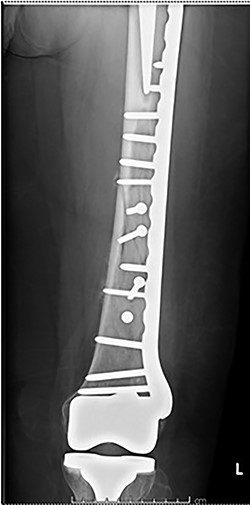

Case 2 (Figs 3–5): here difficulties were clearly encountered in achieving satisfactory reduction in the coronal plane. The screw immediately proximal to the fracture line is too close to the fracture.

Selecting a longer plate would have allowed proximal screws to sit more appropriately in order to reduce the risk of plate fatigue.